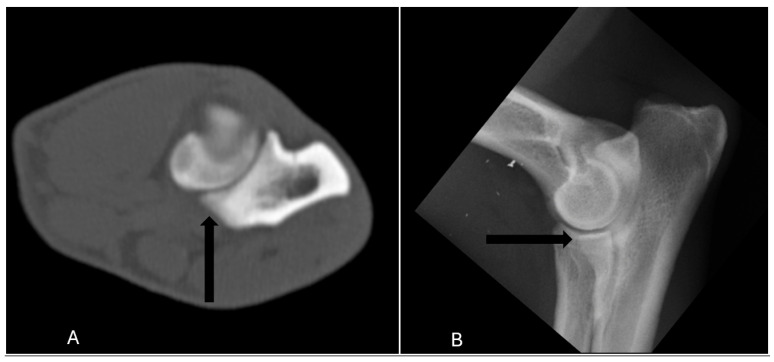

Diagnostic imaging is a crucial non-invasive tool for evaluating canine elbow joints, particularly for screening and treatment planning of medial coronoid disease (MCD). Radiography remains the most accessible and widely used screening modality, but its diagnostic accuracy varies significantly. Sensitivity values reported in previous studies vary depending on factors such as study population, imaging technique, and interpretation criteria. This study compared four measures (sensitivity, specificity, positive and negative predictive value) of radiography with a more advanced imaging method, computed tomography (CT), which provides more detailed images of bones. The results showed that radiography correctly identified 65% of the cases (17/26), while missing some of the affected joints. Furthermore, 7% of the healthy joints (29/398) were misdiagnosed as diseased, leading to a specificity of 93% (369/398). For a disease prevalence of 6% (26/424), the positive and negative predictive value of radiography were 37% (17/46) and 98% (369/378), respectively. Overall, when CT is available, it is the preferred technique for screening. In cases where it is not available, it is important to have an idea of the sensitivity and specificity, but also of the positive and negative predictive value, especially at low prevalences. These results help veterinarians make better decisions when screening for elbow problems in dogs.